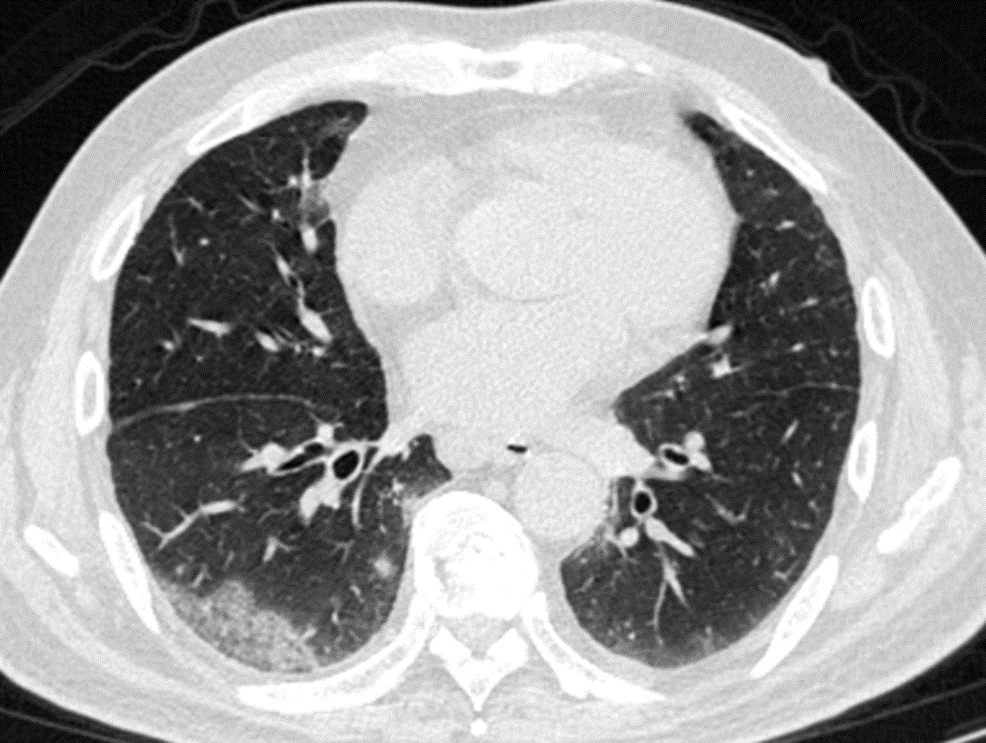

其实,这波omicron感染,确实肺炎比例比想象中要高,但很多都不会是大白肺,多数表现为双肺散发磨玻璃影,当然,也有单独的磨玻璃结节,特别容易表现为混合密度磨玻璃结节。其实很多新发的磨玻璃结节都是新冠肺炎,不用过于紧张,如果感染面积不大,一般临床上,也不需要特异性治疗,休息观察就行了。

可以考虑3个月以后复查一次薄层平扫CT。

CT提示,右肺下叶多发磨玻璃影。